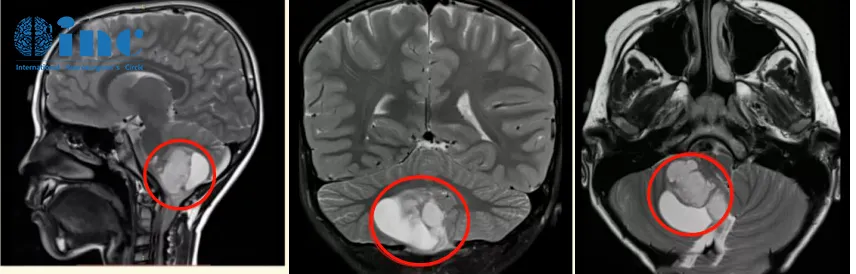

2020年末,6岁的辰辰在一场小小的交通事故后总是抱怨头晕,为明确有没有大脑损伤,担心后遗症,辰辰妈妈带他到医院做了核磁共振,结果竟然查出“小脑占位”,右侧小脑半球见40mm*37mm大小异常信号,邻近四脑室受压变窄,脑干受压,中线结构局部左移。医生给出诊断,考虑可能是低级别的星形细胞瘤。

诊断:小脑毛细胞星形细胞瘤,侵犯右小脑扁桃体、双中央小叶、脑桥臂,脑干受压移位。

术前术后影像对比:术后MR复查显示肿瘤全部切除,无残余,脑干得到充分减压,对中脑的挤压/移位压力明显减少,小脑复位。